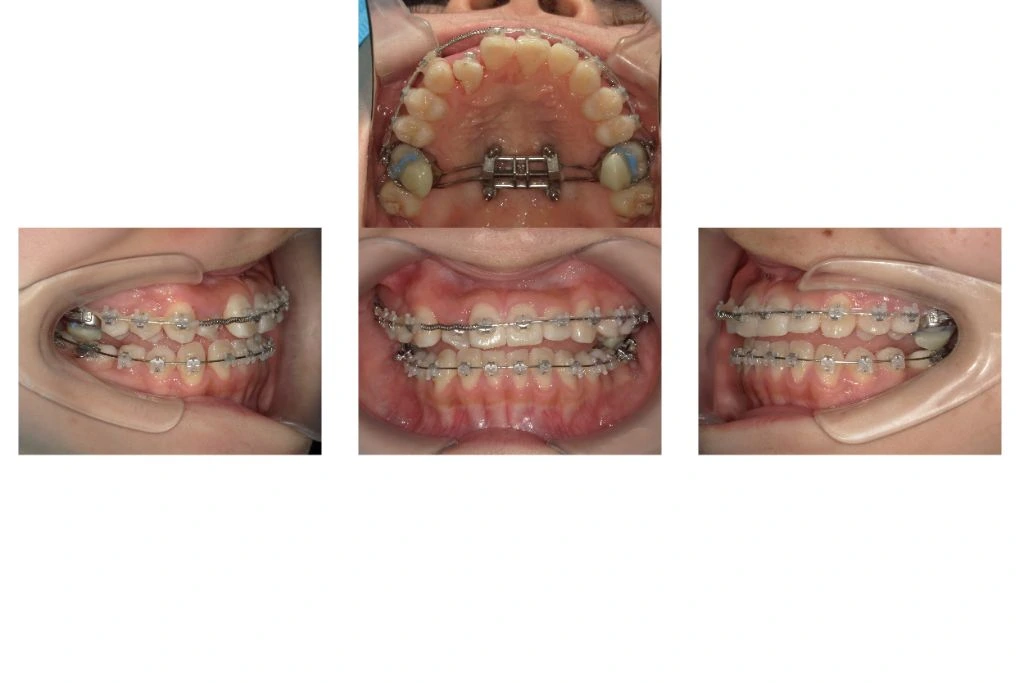

MSEを装着した状態でワイヤー矯正をスタートさせます。オープンコイルを使用しながらスペースを確保しつつ、口蓋側に転位している2番の側切歯を移動させていきます。

【治療後】

MSEを併用しながらワイヤー矯正が終了した状態です。本来の顎位で上下の正中(真ん中)が合ってきて概ね矯正治療としてのゴールが見えてきました。

- 方法:表側セルフライゲーションブラケット(Empower)+シルバーワイヤー+MSE+下顎遠心移動用アンカー2本

- 動的期間:2年